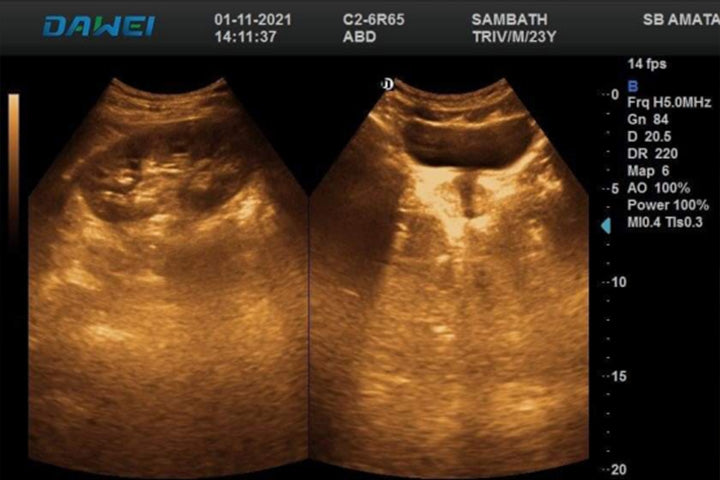

La imagen muestra los comentarios enviados por la Clínica SAMBO AMATA, un hospital privado de Camboya, después de utilizar un nuevo instrumento de ultrasonido portátil 5D especialmente diseñado para mujeres embarazadas: el DW-P5pro. El sueño de Dawei desde hace mucho tiempo es poder enviar un "equipo de asistencia médica que nunca se vaya" a Camboya, y esta retroalimentación es un gran paso en el camino hacia la realización de Dawei.